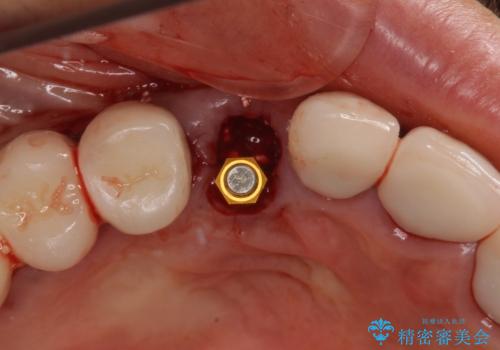

全顎的な治療後に、急遽ニューヨークへ転居されることとなったのですが、治療後から経過観察を行っていた右上犬歯が歯肉縁下に及ぶむし歯のため、クラウンが土台ごと外れてしまったとの連絡がありました。

他の部位にインプラント治療を行っていたことから、こちらの歯に対してもインプラントによる補綴治療を希望されたため、1泊での帰国時に抜歯、インプラント埋入、仮歯の装着を行い、数ヶ月後の帰国時にオールセラミッククラウンの型取りと装着を行う計画としました。

インプラント埋入時は1泊、補綴治療時には3週間ほど日本に滞在していただき、2回の渡航で無事に治療を終えることができました。